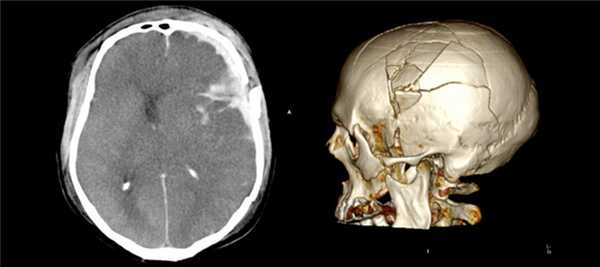

Большим преимуществом КТ перед другими диагностическими методами является возможность получения трехмерной модели височной кости. 3D-изображение необходимо перед хирургическим вмешательством, часто по поводу установки имплантата внутреннего уха, поскольку дает максимально четкое представление об особенностях анатомии у конкретного пациента.